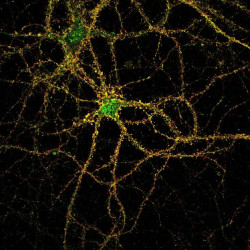

Una investigación liderada por el Instituto de Investigaciones Oftalmológicas Ramón Castroviejo (IIORC), de la Universidad Complutense de Madrid, ha demostrado en un modelo animal la eficacia de combinar las moléculas citicolina y coenzima Q10 (CoQ10) en el tratamiento del glaucoma, una enfermedad degenerativa de la retina que provoca la pérdida progresiva de la visión hasta alcanzar la ceguera.

El glaucoma afectaría a unas 13.000 personas en Cantabria y más de 5.000 aún no saben que lo padecen ya que en sus primeras etapas no presenta síntomas evidentes, según cifras de la Asociación de Glaucoma para Afectados y Familiares (AGAF).